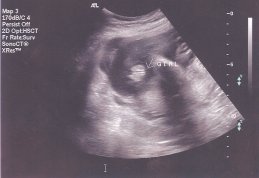

Улыбка писал(а): Аничка, спасибо еще раз, зая! Время так быстро бежит! Даже не верится, что у тебя уже 33 недели!!! Ой Улыбка и не говори.Мне чем ближе срок тем страшнее становится.Больше всего боюсь как моя 2-х летка дочка к братику отнесётся,чувствую 5 точкой ревновать будет по страшному.Она уже как обезьянка на мне в последнее время виснет,везде по пятам да и на ручки просится постоянно.Не было такого у нас раньше,прям как чувствует что ли. Смотри я кстате фотку с дочкиного УЗИ откопала,почти такой же ракурс,ПИРОЖОЧЕК

| Вложения: |

scan0001.jpg [ 16.08 КБ | Просмотров: 1298 ]

anichka писал(а): Смотри я кстате фотку с дочкиного УЗИ откопала,почти такой же ракурс,ПИРОЖОЧЕК  Возможно, что в таком же ракурсе у мальчика будет тоже пирожочек  , но он будет другой, эта полосочка, которая проходит посередине пирожочка будет белая , а у девочек она черная между двух беленьких (думаю понятно объяснила  ).